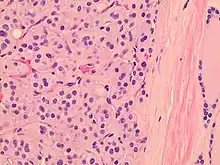

| Histopathology of a Hürthle cell adenoma | |

Hürthle cells are characterized as enlarged epithelial cells. These cells, when stained with hematoxylin-eosin show as pink. This is due to the abundant mitochondria and granular eosinophilic matter within the cells' cytoplasm. These cells are often found in the thyroid. The thyroid is a butterfly-shaped organ, responsible for producing various hormones for metabolism. These cells are often benign, but they can be malignant and metastasize. Hürthle cells are resistant to radiation, but can be treated using radioactive iodine treatment.[4]